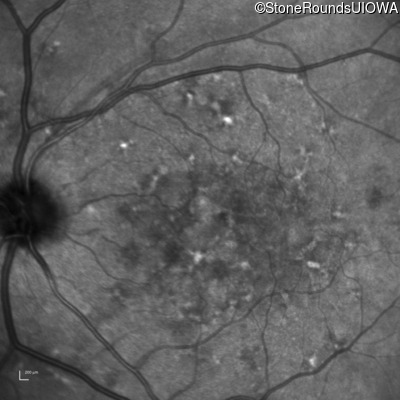

Fluorescein Angiography - Right - 20/250

Exemplar